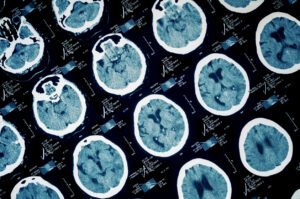

Approximately 50 million people around the world sustain a traumatic brain injury (TBI) each year — a growing percentage of those cases are due to cycling crashes — and still, there is a lack of consistency in treatment and follow-up care.

While the cause of a TBI can happen in an instant, the recovery can take weeks or months and symptoms may linger for just as long. TBIs are notoriously difficult to diagnose and can even be misdiagnosed, leading to longer recovery times.

What qualifies as a TBI and its severity is not the same across the board. Researchers at the JFK Johnson Rehabilitation Institute note that a variety of organizations, from the CDC to the World Health Organization to the American Congress of Rehabilitation Medicine all have differing definitions for mild TBIs.